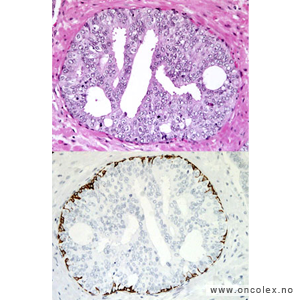

Bildeeksempler av vevsprøver

Gleasongraderinger

Ved prostatakreft anvendes et særskilt graderingssystem som ble beskrevet av patologen Donald Gleason i 1966. Dette samsvarer sterkt til prognosen. I motsetning til WHO baserer Gleasongradering/Gleason score (GS) seg kun på kjertlenes arkitektur og cellenes sammensetning, ikke cellenes atypi. De senere årene har ISUP gradering kommet i bruk, det er forsåvidt en forenkling av GS med et tall fra 1-5 hvor ISUP 1 = GS6, ISUP 2 = GS 7a, ISUP 3 = GS7b, ISUP 4 = GS8 og ISUP 5 = GS 9 og 10.